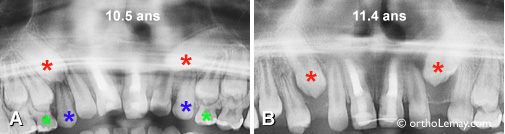

Il est possible de confirmer radiologiquement qu’une suture maxillaire se sépare correctement comme l’illustrent les exemples ci-dessous. Il est cependant rare d’avoir à prendre de telles radiographies.

Amélioration significative de la position des canines supérieures permanentes (* rouge) après l’extraction sélective des canines temporaires (* bleu) et des premières molaires temporaires (* vert). Ces changements se sont produits en moins d,une année. Sans cette intervention, il y avait de fortes chances que les canines permanentes se soient dirigées vers le palais et deviennent sévèrement incluses.

asymétrie aux deux arcades

Asymétrie aux deux arcades dentaires causée par la perte de dents temporaires chez un garçon de 11.5 ans. Des extractions sélectives ou pilotées sont indiquées pour aider l’éruption des autres dents et tenter de restaurer une certain symétrie aux arcades.